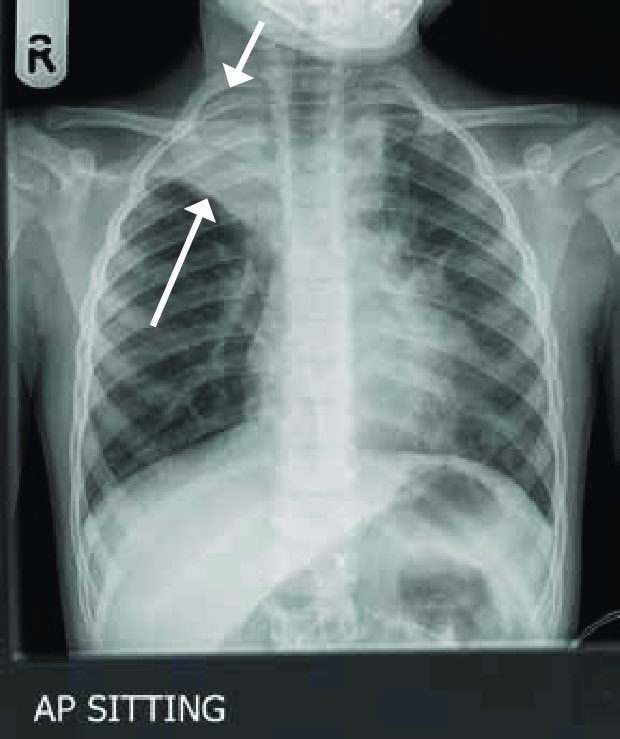

خراج الرئة

هواء بالرئة

** اذا الأزرق صديد نسميه خراج وإذا هواء نسميه الريح الصدرية